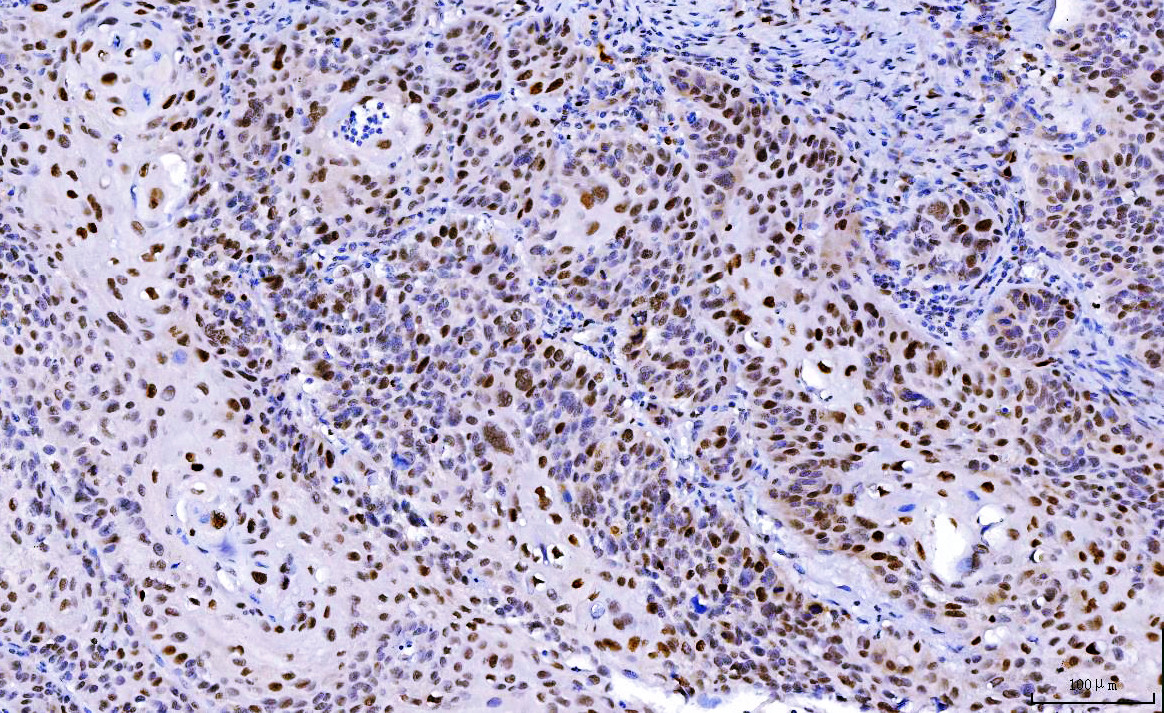

IHC analysis of CDK2 using anti-CDK2 antibody (M00166-3).

CDK2 was detected in a paraffin-embedded section of human Laryngeal squamous cell carcinomas tissue. Biotinylated goat anti-mouse IgG was used as secondary antibody. The tissue section was incubated with mouse anti-CDK2 Antibody (M00166-3) at a dilution of 1:200 and developed using Strepavidin-Biotin-Complex (SABC) (Catalog # SA1021) with DAB (Catalog # AR1027) as the chromogen.